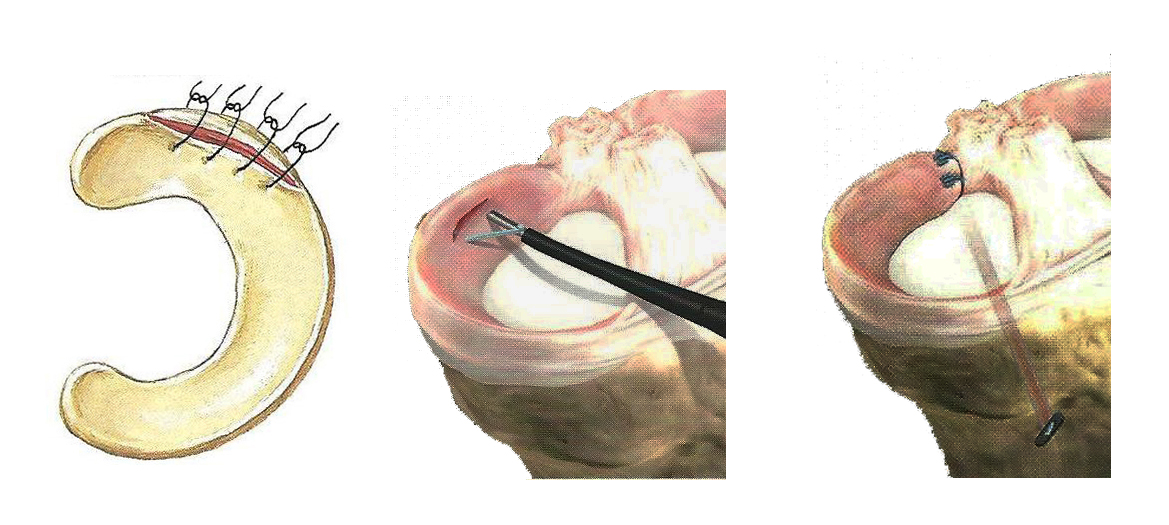

Όσον αφορά στην συρραφή του μηνίσκου (εικόνα 5) οι ενδείξεις και τα αποτελέσματα είναι ξεκάθαρα. Απόλυτη ένδειξη και καλύτερα αποτελέσματα έχουν οι περιφερικές ρήξεις που συμβαίνουν στην αγγειούμενη περιοχή του μηνίσκου (τη λεγόμενη “κόκκινη ζώνη”), ενώ σχετική ένδειξη έχουν οι συρραφές στην περιοχή μετάπτωσης αγγειούμενης και μη περιοχής (τη “λευκή ζώνη”).